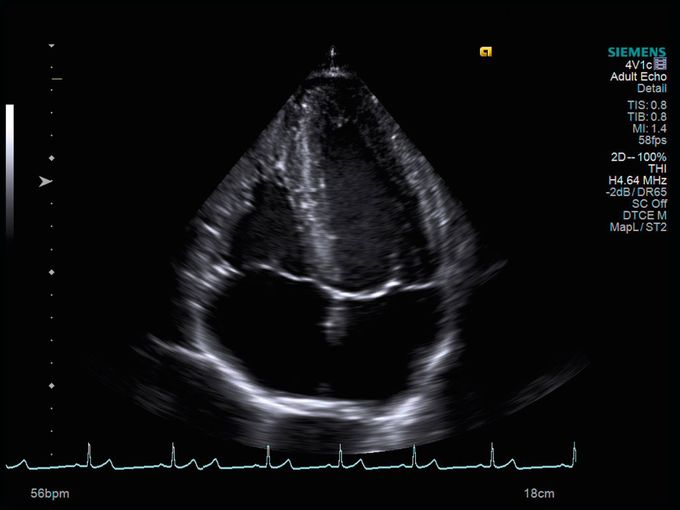

Кроме новой техники, можно заказать восстановленные медицинские системы: ультразвуковые сканеры, томографы, флюороскопы, ангиографы и хирургические установки С-дуга.